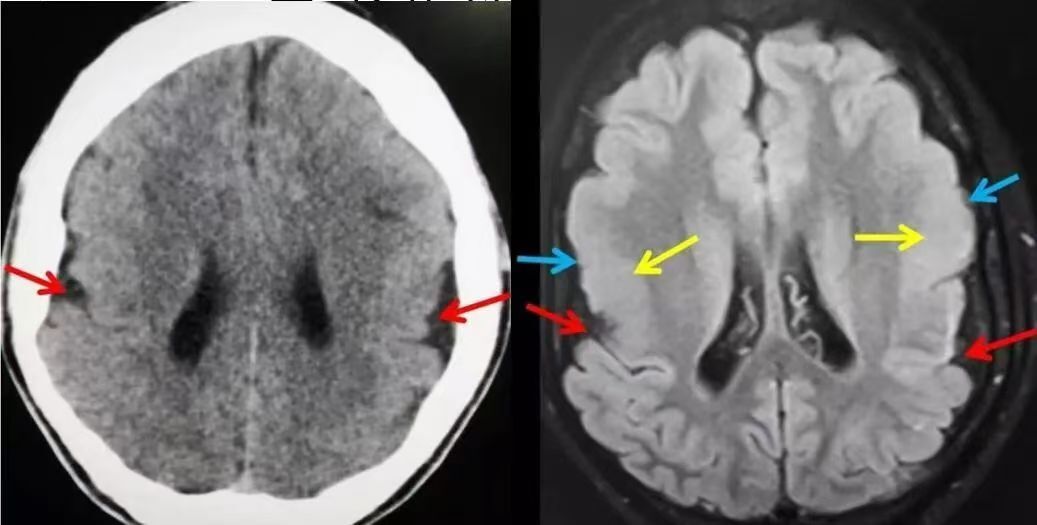

(五)CT扫描 能直观地显示脑穿通畸形的存在及类型,对了解囊肿的大小、部位、形态、数目及治疗方案选择、预后估计、鉴别诊断等均有重要意义。CT表现脑内囊肿性病变,CT值与脑脊液相似,病灶部位低密度影,与脑室相通。其他表现有脑积水、脑皮层萎缩等。强化扫描不增强。

(六)核磁共振(MRI) 呈长T1和长T2象,常与脑脊液一样,在T1加权象上呈囊状低信号,在T2加权象上呈高信号。